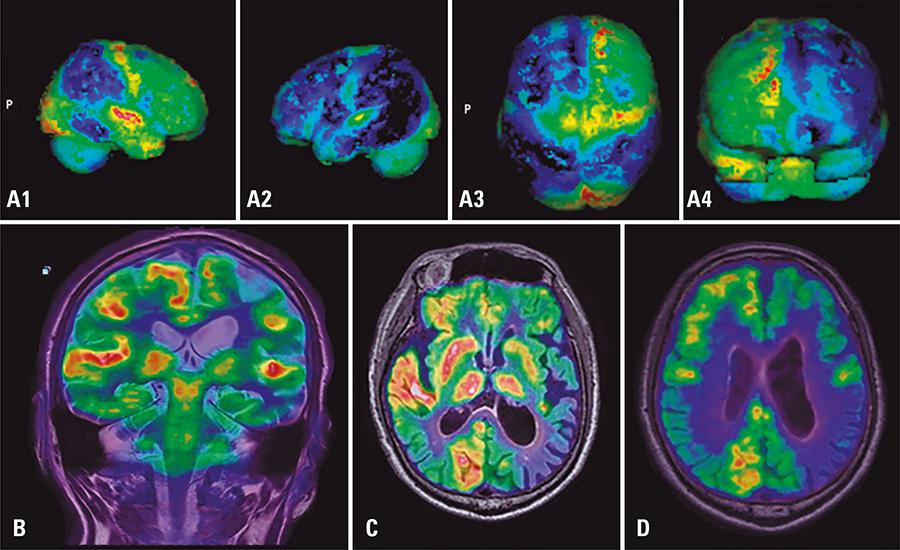

In recent years, medical imaging with hybrid techniques has widely accepted and employed in clinical routine. PET/MRI offers significant advantages, including excellent contrast and resolution and reduced ionizing radiation, as compared to well-established PET/CT. Therefore, PET/MRI is a promising modality for oncologic imaging of some regions, such as brain, head and neck, liver and pelvis. This article set out to analyze clinical conditions that could benefit from PET/MRI imaging based on our caseload. The potential of PET/MRI to become the imaging modality of choice for assessment of neurologic and oncologic conditions associated with soft tissues is highlighted. Clinical aspects of PET/MRI and its application to clinical cases are illustrated with examples extracted from the authors’ preliminary experience.